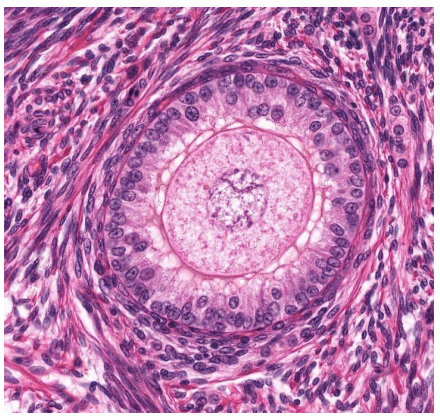

red

granulosa cells

orange

primary oocyte

what is this

primary follicle